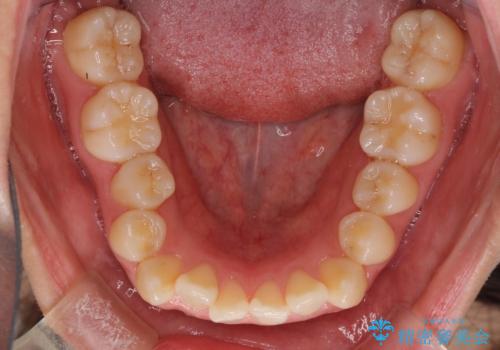

- 前歯のデコボコとクロスバイトを気にして来院された患者様です。

骨格的に下顎が前方位の受け口傾向であり、それが原因でクロスバイトとなっていました。

右奥の歯が180度回転していることで、噛む度にワイヤーに無理な力がかかったようで、頻繁にワイヤーが切れてしまいました。また、下顎を後方に移動させるためのアンカースクリューも脱離することが多く、治療期間が長くなってしまいました。